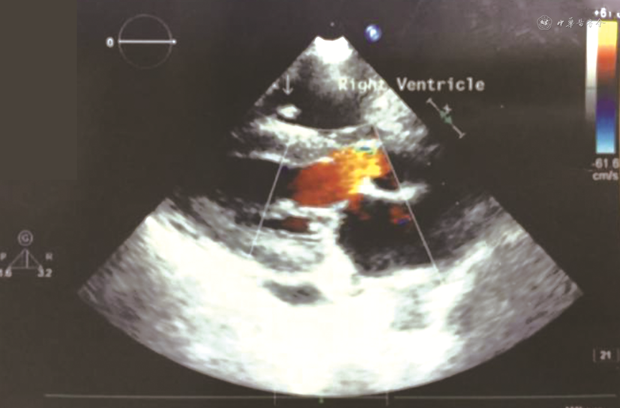

2020年12月1日复查肺CT,炎症进一步吸收,但患者仍高热,心脏查体二尖瓣区可闻及收缩期2级吹风样杂音,经胸超声心动图(TTE)瓣膜反流较前无明显变化,肺动脉收缩压升至65 mmHg,未见赘生物,调整为美罗培南2 g/次、3次/d静脉滴注,环丙沙星400 mg/次、2次/d静脉滴注,阿米卡星0.4 g/次、2次/d静脉滴注,利福平600 mg/次、1次/d口服,达托霉素360 mg/次、1次/d静脉滴注,磺胺0.48 g/次、1次/d口服联合伏立康唑200 mg/次、2次/d静脉滴注抗感染治疗,体温仍不能控制。2020年12月7日再次出现42℃的体温高峰,将阿米卡星调整为乙胺丁醇并停用伏立康唑,2020年12月8日仍因血小板低下难以承受经食管超声心动图(TEE),再次TTE检查,右心室内探及多个低-中等回声团块,附着于三尖瓣前叶腱索上,最大约16.0 mm×7.3 mm(图2),活动度小,左心室内探及低-中等回声团块,约2.8 mm×3.6 mm,附着于二尖瓣外乳头肌上,活动度小,瓣膜反流较前无明显变化,肺动脉收缩压降至35 mmHg。患者感染性心内膜炎(IE)诊断明确,有手术指征、需行瓣膜置换术,但因血小板明显减少无法手术治疗。2020年12月8日复查肺CT可见新发炎症,患者经多种抗生素治疗后,二尖瓣反流较前下降,肺动脉压有所回落,但体温仍未能控制,2020年12月13日患者自动出院。